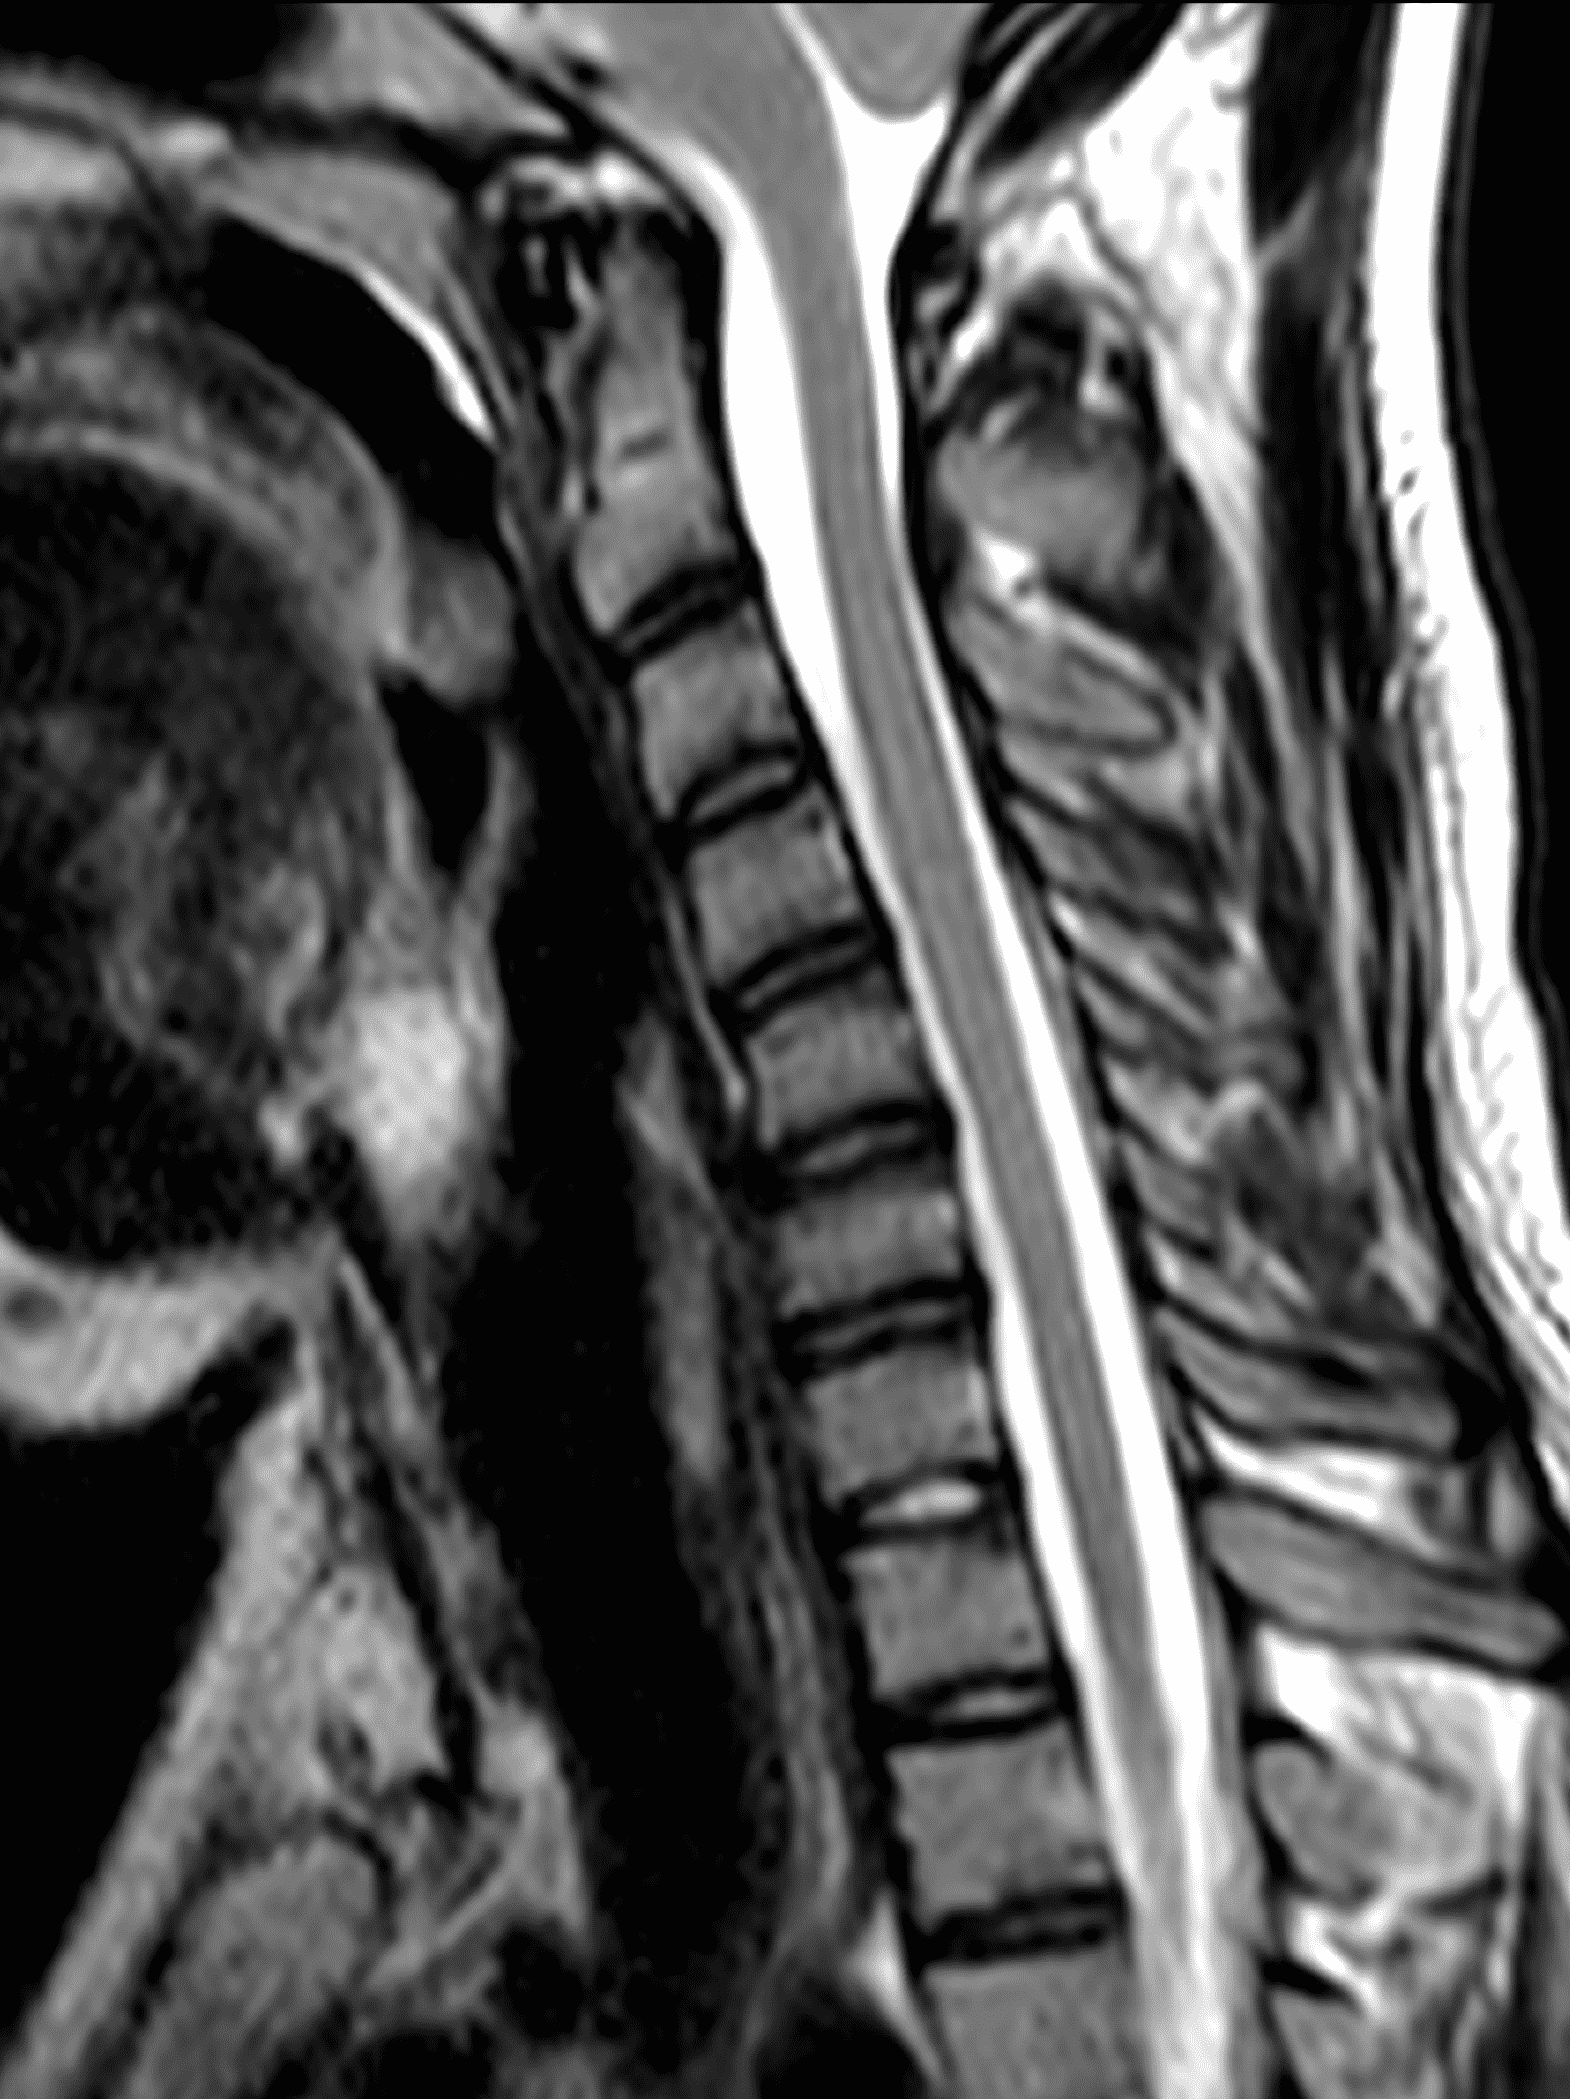

An 18 year old man presents with progressive motor wasting of right hand, progressive right hand weakness, claw-like deformity with flattening of the hand, and inability to straighten the ring and small fingers. He reports no numbness or pain. Sagittal T2-weighted (1A), sagittal T1-weighted (1B), sagittal STIR (1C), axial T2-weighted (1D), and axial T1-weighted (1E) images of the cervical spine obtained around the time of presentation are provided. What are the findings? What is your diagnosis?

Figure 2: Neutral images of the cervical spine. Sagittal (2A) T2-weighted, (2B) T1-weighted, and (2C) STIR images show mild kyphosis, an enlarged posterior epidural space with loss of attachment of the dura (red arrows), and cord atrophy at the C6 level (yellow arrow). Subtle cord hyperintensity on the water sensitive images at the C7 level (green arrows) likely represents gliosis. (2D) Axial T2-weighted image shows enlargement of the posterior epidural space, right greater than left (red arrows). (2E) Axial T1-weighted image shows an enlarged posterior epidural space (red arrows) and cord atrophy, more severe on the right (yellow arrow).